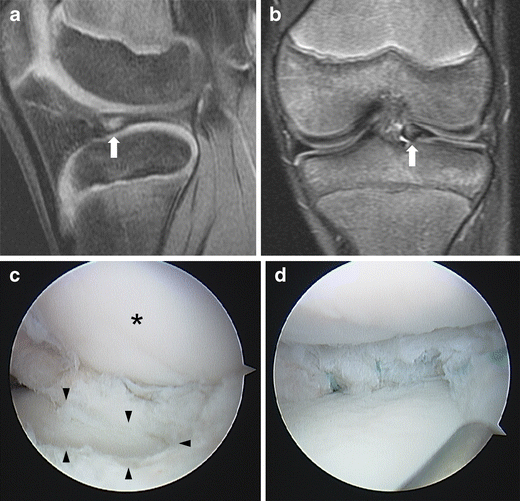

Figure 1 from Spontaneous Healing of a Displaced BucketHandle Tear of Bucket Handle Tear Discoid Lateral Meniscus it causes pain, locking, popping, joint swelling, joint instability, and other symptoms. a bucket handle meniscus tear is a serious injury that results in the meniscus tearing and flipping in the joint. Surgery is often necessary, but your healthcare provider may recommend less invasive measures. It can be extremely painful and cause knee locking. tie sutures against. Bucket Handle Tear Discoid Lateral Meniscus.